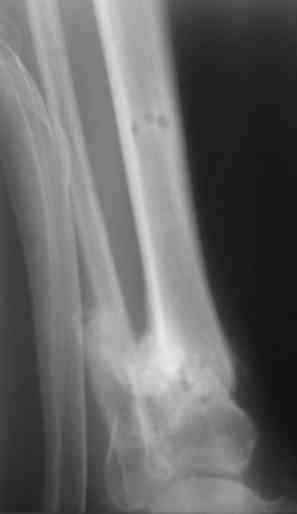

У меня сейчас лечится похожий пациент - ему стрельнули в упор из охотничьего ружья: открытый скозной перелом правой голени в н/3 с дефектом костной ткани до 6 см. При поступлении наложили ап.Илизарова. После отторжения всех некрозов и несмотря на сохраняющиеся раны (чтобы не терять время) мы провели повторную операцию - наростили аппарат Илизарова вверх на одно кольцо, под которым сделали поперечную остеотомию большеберцовой кости (в проксимальном метафизе) и теперь низводим образовавшийся промежуточный фрагмент по 1-2 мм в сутки при сохранении общей длины конечности. В месте остеотомии растет регенерат, который постоянно рентген-контролируем. Думаю что это самый лучший вариант для подобного рода травм. Если будет интересно могу показать снимки (как раз скоро очередной рентген-контроль).

Есть у меня результат такого метода. Тема обсуждалась. Как говорится - лечили всем форумом. Рана, правда, не огнестрельная - OFFтопик.

Больной случайно попал в поле зрения с переломом шейки бедра. Страдает хр. алкоголизмом. От когда-то предложенного удлиннения голени пациент отказался. После снятия аппарата он пропал как с белых яблонь дым ...

Укорочение конечности 3 см. Передвигался без дополнительной опоры с "нарощенной" подошвой на правой обуви. Ограничение тыльного и подошвенного сгибания - умеренные (всего примерно 50%, не измерял).